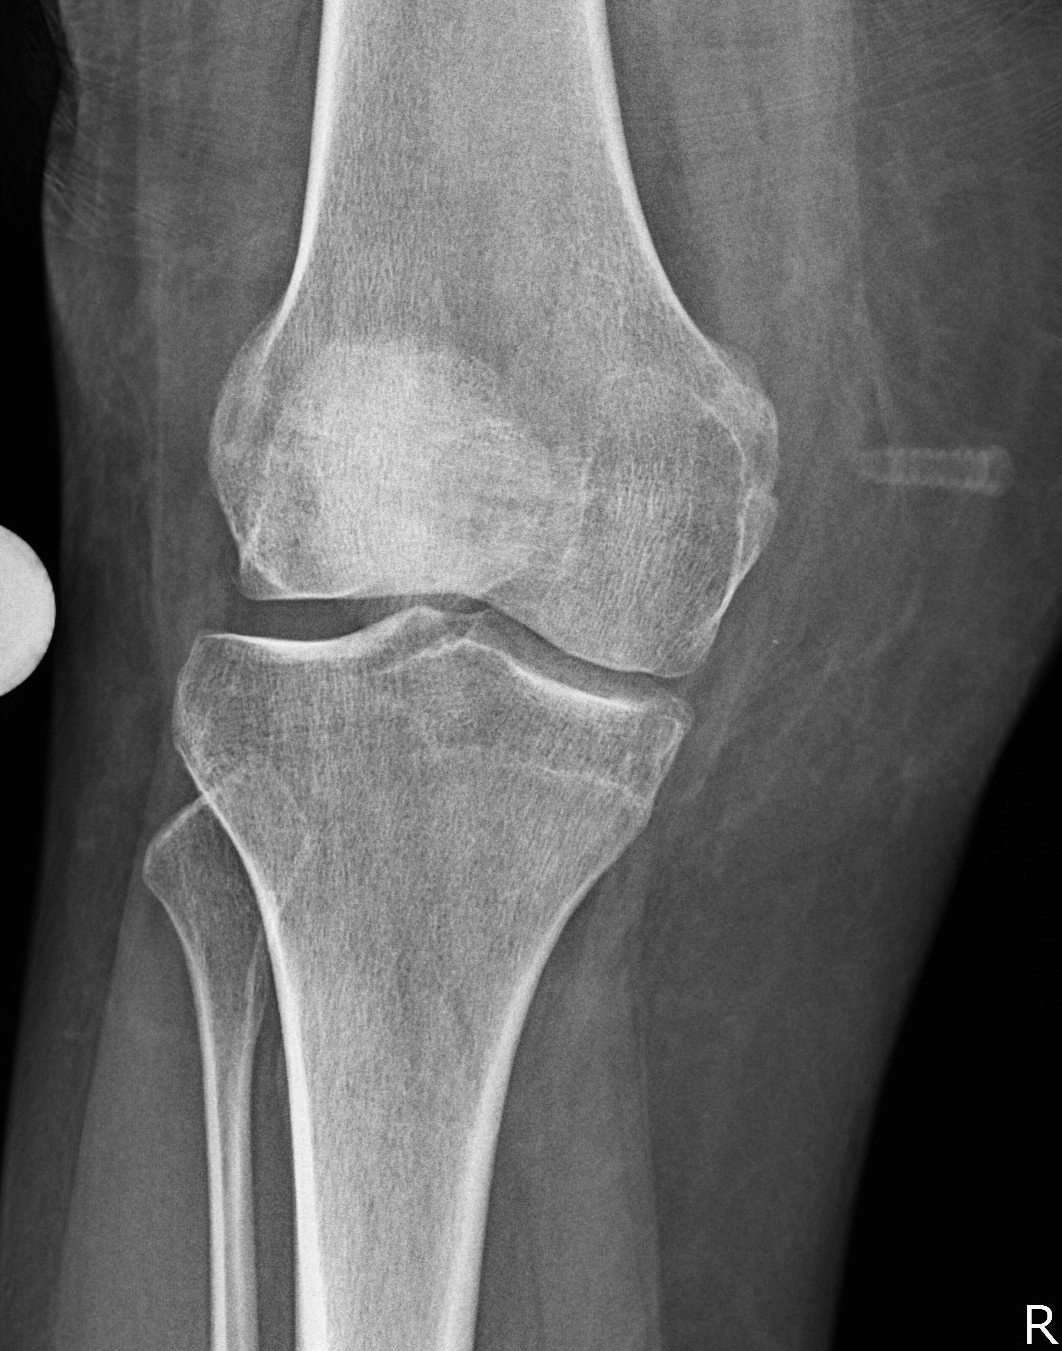

- clinical and xray patella tilt

- excessive lateral pressure syndrome